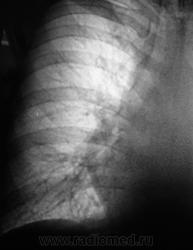

1 срез.